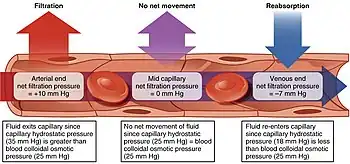

Starling equation

The transport mechanisms can be further quantified by the Starling equation.[20] The Starling equation defines the forces across a semipermeable membrane and allows calculation of the net flux:

where:

- is the net driving force,

- is the proportionality constant, and

- is the net fluid movement between compartments.

By convention, outward force is defined as positive, and inward force is defined as negative. The solution to the equation is known as the net filtration or net fluid movement (Jv). If positive, fluid will tend to leave the capillary (filtration). If negative, fluid will tend to enter the capillary (absorption). This equation has a number of important physiologic implications, especially when pathologic processes grossly alter one or more of the variables.

According to Starling's equation, the movement of fluid depends on six variables:

- Capillary hydrostatic pressure (Pc)

- Interstitial hydrostatic pressure (Pi)

- Capillary oncotic pressure (πc)

- Interstitial oncotic pressure (πi)

- Filtration coefficient (Kf)

- Reflection coefficient (σ)